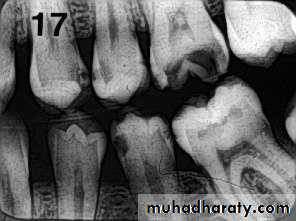

Carious lesions are detectable radio graphically when there has been enough demineralization to allow it to be differentiate from normal.They are valuable in detecting proximal caries which may go undetected during clinical examination.

On average they have around 50% to 70% sensitivity in detecting carious lesions.

40% demineralization is required for definitive decision on caries

PIT & FISSURE CARIES

Incipient occlusal lesions:Not very effective.

Caries starts on the walls

of the pits & fissures and

tends to spread

perpendicular to the DEJ

Only detectable change is

a fine gray shadow at the

DEJ.

Moderate occlusal lesions:

Moderate occlusal lesions: First to induce specific changes

helping in a definitive diagnosis

Broad based, thin radiolucent

zone in dentin with minimal or

no changes in enamel

Presence of a band of increased

opacity between the lesion and

the pulp chamber due to

calcification within primary

dentin

This feature is not seen in

buccal caries

Severe occlusal lesions:

Readily observed bothclinically and

radiographically

Appear as large cavities in

the crowns of the teeth

However pulp exposure

cannot be determined

Incipient occlusal lesions

Moderate occlusal lesionsSevere occlusal lesions

Advanced proximal lesions

Incipient proximal lesionsModerate proximal lesions